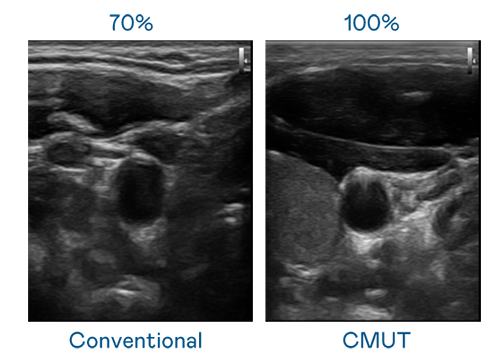

CMUT 技术是一种用电容式微机电元件来产生超音波讯号的技术。与传统 PZT 压电式技术相比,CMUT 频宽增加 30%,更宽频的超音波讯号让影像解析度大幅提升,是实现高影像品质医疗超音波扫描、促进精准医疗发展的关键技术。

大频宽带来超清晰影像

超音波影像的解析度高低,首先取决于探头能发出的讯号频宽。必威betway CMUT 可提供高清晰的超音波讯号,提供高频宽、高灵敏度、影像纹理细节更高的超音波影像,协助医护人员缩短影像判读时间及利用精准的医疗影像进行诊断。